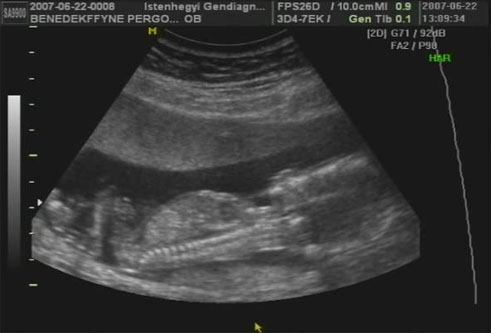

Uh.: Alex: 1340 g. Anna: 1218 g. Szoval szepen novekednek a bebik es mar csak 1 hetnyi kulonbseg van de az lofutty! Oriasbebik nem lesznek de sebaj! Alex csucsul, Anna keresztben van es mondta a doki valoszinu ebbol csaszar lesz de ez nem erdekel csak jol legyenek!

KépKép

Szupik az adatok, nem is baj, ha nem óriásbébik, mi lenne akkor veled a végén...

Szuper hírek! Nagyon szépen fejlődnek a bébik! Gratula hozzájuk. Látod, hogy megijesztett néhány hete a kislány, aztán milyen szépen fejlődik! Nagyon-nagyon örülök! :)